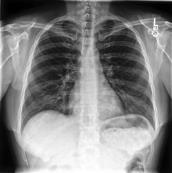

Large numbers of labeled medical images are essential for the accurate detection of anomalies, but manual annotation is labor-intensive and time-consuming. Self-supervised learning (SSL) is a training method to learn data-specific features without manual annotation. Several SSL-based models have been employed in medical image anomaly detection. These SSL methods effectively learn representations in several field-specific images, such as natural and industrial product images. However, owing to the requirement of medical expertise, typical SSL-based models are inefficient in medical image anomaly detection. We present an SSL-based model that enables anatomical structure-based unsupervised anomaly detection (UAD). The model employs the anatomy-aware pasting (AnatPaste) augmentation tool. AnatPaste employs a threshold-based lung segmentation pretext task to create anomalies in normal chest radiographs, which are used for model pretraining. These anomalies are similar to real anomalies and help the model recognize them. We evaluate our model on three opensource chest radiograph datasets. Our model exhibit area under curves (AUC) of 92.1%, 78.7%, and 81.9%, which are the highest among existing UAD models. This is the first SSL model to employ anatomical information as a pretext task. AnatPaste can be applied in various deep learning models and downstream tasks. It can be employed for other modalities by fixing appropriate segmentation. Our code is publicly available at: https://github.com/jun-sato/AnatPaste.